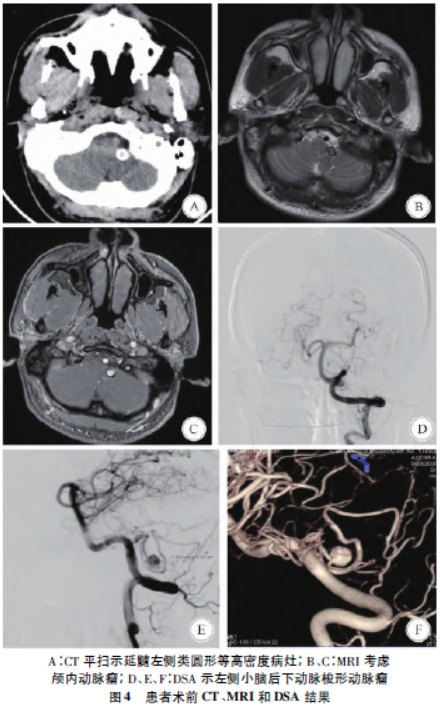

患者男,36岁,因“反复头晕1月余伴呕吐”于2020年7月入院。1月余前患者无明显诱因下出现头晕,伴呕吐,时无心慌、胸闷、耳鸣、耳聋等,经休息后症状缓解,当时并未在意。后头晕症状反复发作,至当地医院头颅CT检查

示,延髓左侧方见一圆形等高密度病灶,瘤壁钙化。行头颅MRI检查,怀疑左侧小脑后下动脉瘤,进一步行DSA检查示,左侧小脑后下动脉扁桃体延髓段动脉瘤(图4)。